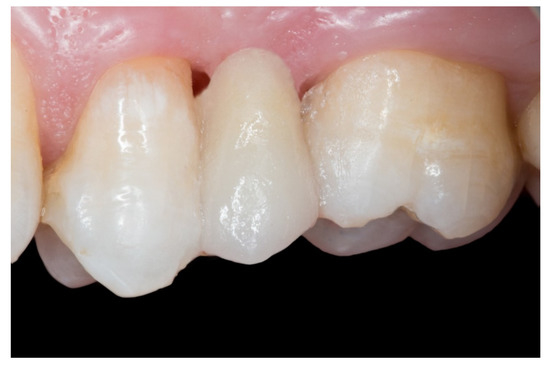

Figure 7.

The FRCB after the occlusal adjustment and composite polishing.

Figure 8.

The embrasures are released allowing adequate interproximal brushing, avoiding periodontal disease and interproximal caries.